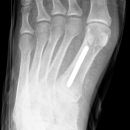

Nagel im Fuß